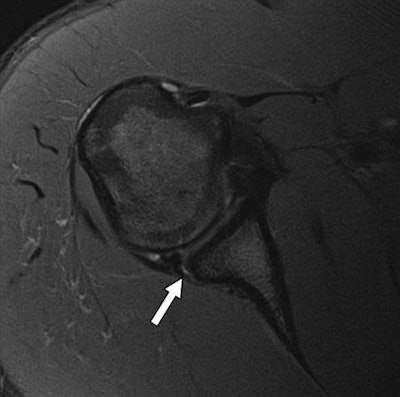

MRI is considered the modality of choice to evaluate shoulder conditions such as rotator cuff tears, labral abnormalities, and other causes of shoulder pain. The downside of MRI is that cost and scanner availability can limit its use, the authors wrote (AJR, April 2017, Vol. 208:4, pp. W146-W154).

To compare scan times and subsequent image quality, standard 2D FSE shoulder MR sequences were immediately followed by the fast five-minute parallel imaging technique. Among the subjects, 66 were being scanned for unknown shoulder pain, 49 for rotator cuff tears, and 22 for labral tears or biceps tendon abnormality.

Both imaging techniques achieved similar rates of detection for major abnormalities. For example, 102 (75%) of 135 full-thickness shoulder tears and 32 (68%) of 47 complete biceps tendon tears were detected by both protocols (p ≥ 0.08 for each structure).

In addition, sensitivity for the five-minute MRI protocol was equal to or better than sensitivity for the standard MRI technique for every structure except glenohumeral cartilage defects, which were limited by a small sample size on the 1.5-tesla scanner, the researchers noted.